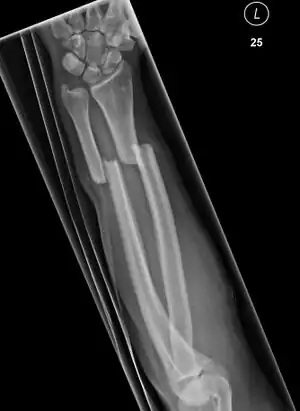

Front view of bowing fractured radius and ulna

Side view of bowing fractured radius and ulna